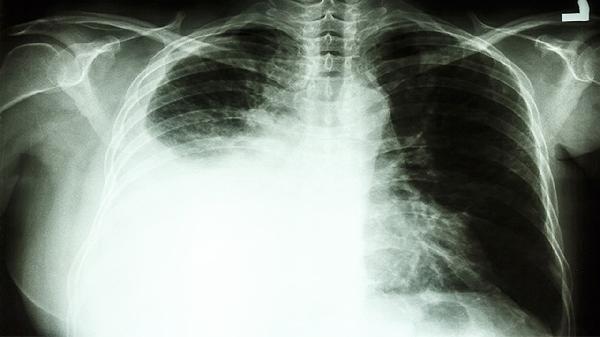

1、CT报告上的"磨玻璃影"

小于5mm的结节通常只需随访,但伴有分叶、毛刺等特征要警惕。

2、肺功能检查数值

FEV1/FVC比值低于70%提示可能存在阻塞性通气障碍。

3、肿瘤标志物波动

单项指标轻度升高不必恐慌,要结合影像学综合判断。